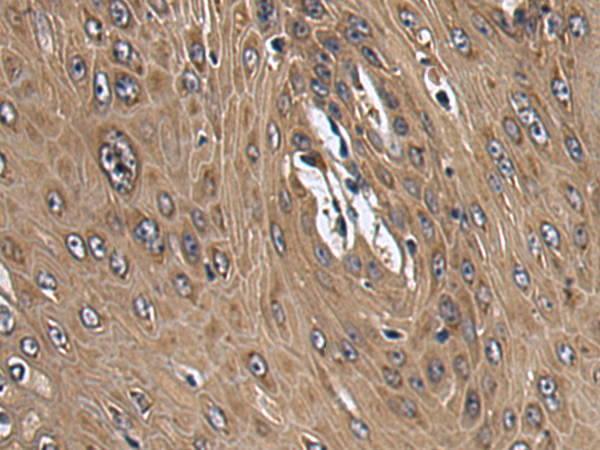

IHC positive control: |

Human colorectal cancer and Human esophagus cancer |

IHC Recommend dilution: |

150-300 |